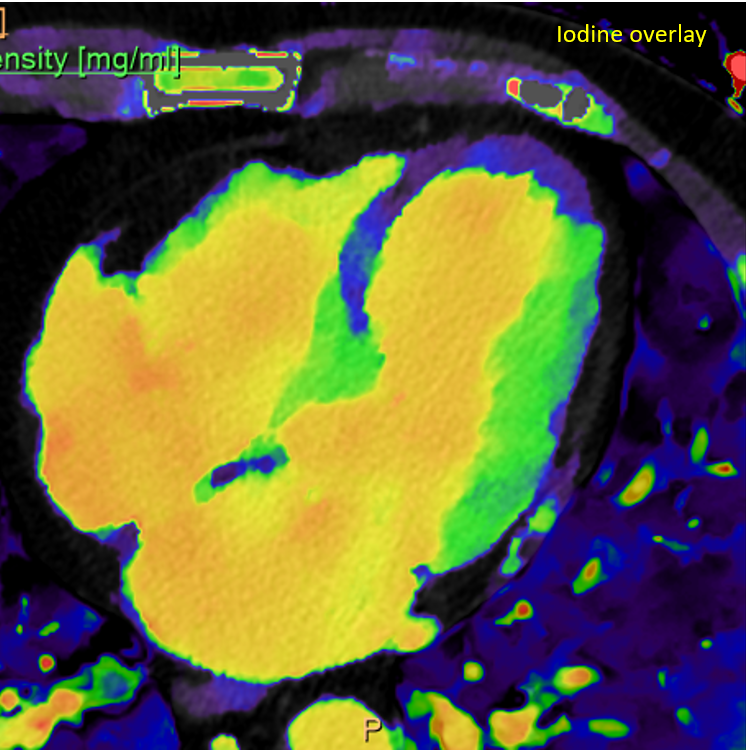

Attention to #spectral images! Gopal Punjabi ⚠️ The endobronchial content is enhancing --> solid! 1️⃣Virtual non-contrast (VNC)= 39HU 2️⃣Conventional= 71UH (>20UH compared to VNC) 3️⃣ Iodine density =1.26 mg/ml